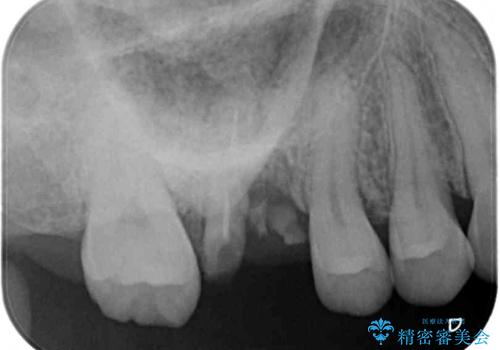

- 歯がほとんどなくなってしまうまで虫歯を放置してしまったとのことで来院された患者様です。

抜歯が必要であることは患者様自身も理解されており、インプラントによる欠損補綴治療を希望されていらっしゃいました。

抜歯前のCTにより、インプラントを埋入するために必要な歯槽骨量が不足することが予想されたため、サイナスソケットリフトにより上顎洞内の粘膜を挙上して、インプラントを埋入することとしました。

虫歯を放置した期間が長かったため、対合の下顎大臼歯が上顎に迫ってきており、咬み合わせは非常にシビアでした。